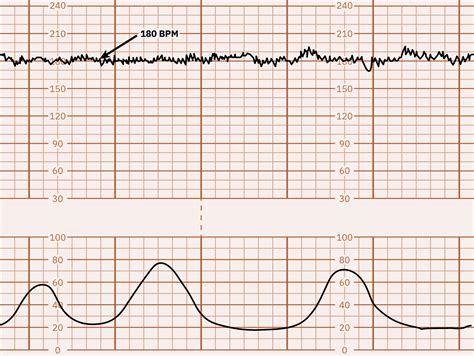

Figure 2 from Sinusoidal Fetal Heart Rate Pattern After Administration ...